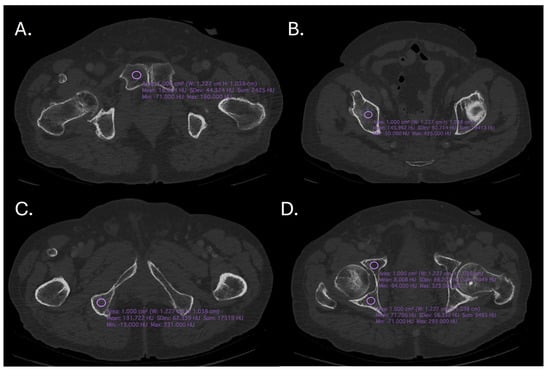

2. Materials and Methods